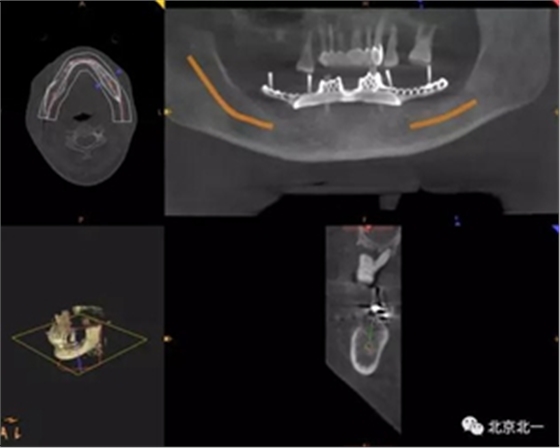

圖一:術(shù)前CBCT

圖二:術(shù)前數(shù)字化設(shè)計(jì)種植導(dǎo)航手術(shù),設(shè)計(jì)導(dǎo)板

圖二:術(shù)前模擬導(dǎo)板 , 精準(zhǔn)植入。